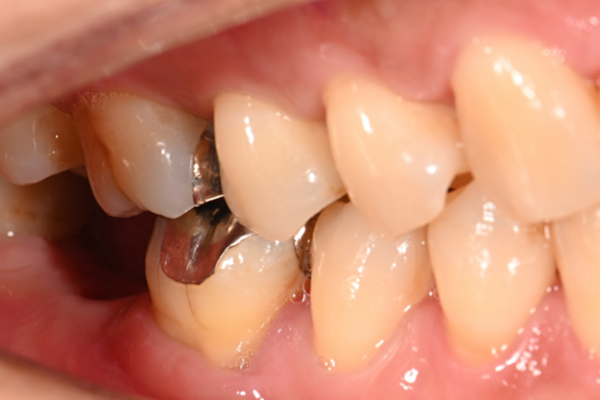

| 主訴 | 奥歯で噛めない、顎が痛い |

|---|---|

| 治療内容 | 奥歯のインプラント治療、前歯・奥歯の被せ物治療 |

| 治療期間 | 6ヶ月 |

| 治療費 | 350万円 |

| 治療リスク | 被せ物をつけた初期の段階で歯がしみることがある(時間とともに改善する) インプラント治療後に3日程度痛みと腫れを伴うことがある |